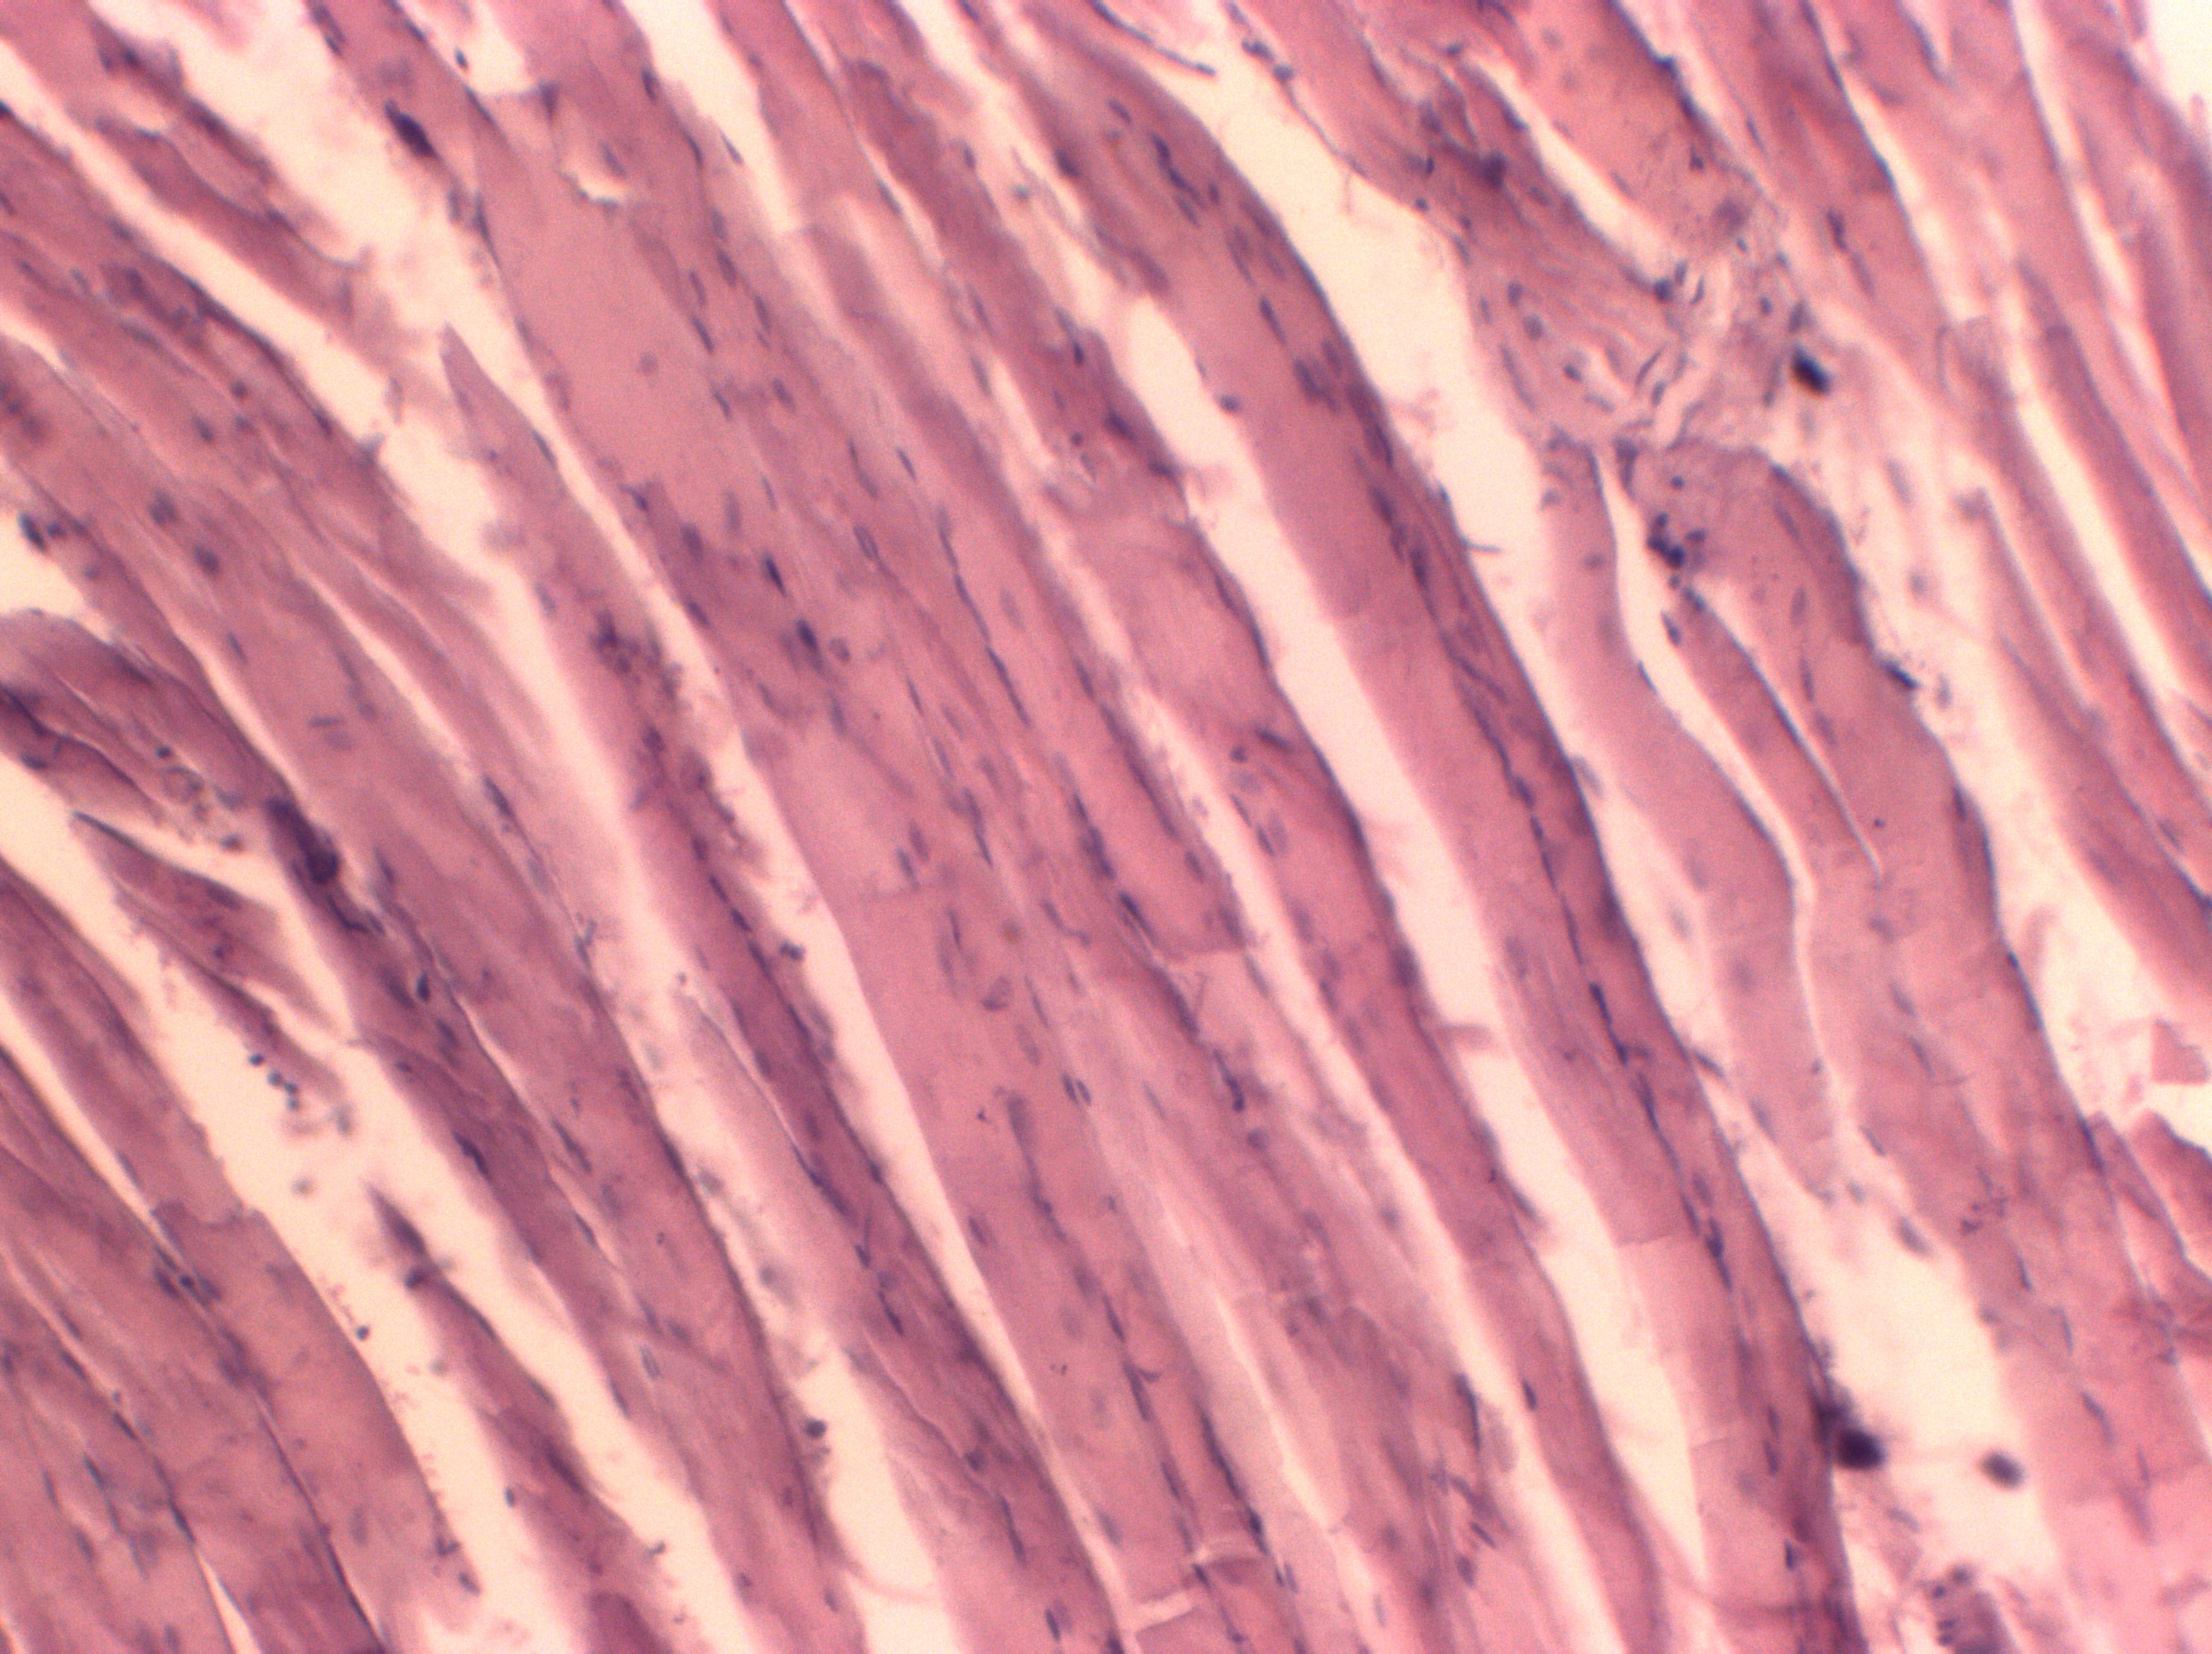

Results and Discussion. All-round analysis of the obtained data revealed that the pathological changes in muscle tissue were aroused in the early period of the postischemic lesions and increased to the end of the 1st day. Histological examination revealed the following changes in the muscle tissue: disorganization of the structural components of the muscle cells, reduction of the striation, friability, fluffiness and rupture of the muscle fibers, violation of their sinuosity, nonlinear arrangement of the nuclei, appearance of the detached necrotic regions and location of the nuclei in the intercellular space. The most significant edema of the muscle tissue occurred on the 1st day in the third group of rats ((41.73±0.39) μm). The average diameter of the muscle fibers in this group was exceeded by 3.37 % the corresponding index ((40.37±0.54) μm) of the control group (P˂0.05). The average area of the nuclei of the muscle fibers ((64.03±0.08) μm) in the third group was only slightly higher than the corresponding value ((63.95±0.07) μm) of the control group (P<0.05). The detected decreasing in the nuclearytoplasmic ratio in the second (0.047±0.001) and the third (0.047±0.001) groups of rats compared with the corresponding indicator of the control group (0.050±0.001) (p˂0.05) may indicate the decreasing in the cellular nuclear activity in the result of ischemic injury.

Conclusions. The results of remodeling of the muscle fibers and the blood vessels of the microcirculatory bed confirm the development of ischemic-reperfusion syndrome in experimental animals. In study of the skeletal muscles of the hind limbs of the white rats after acute ischemia caused by the application of the tourniquet, it was found that the remodeling of the muscle fibers was mainly manifested by edema, homogenization of sarcoplasm, violation of linear arrangement of nuclei in the myocytes and leukocyte infiltration of endoand perimizia, myolysis with the destruction of the sarcolemma and the release of nuclei into the intercellular space. The reactive lesions were developed in the microvessels of all segments and maximally expressed by the end of the 1st day.